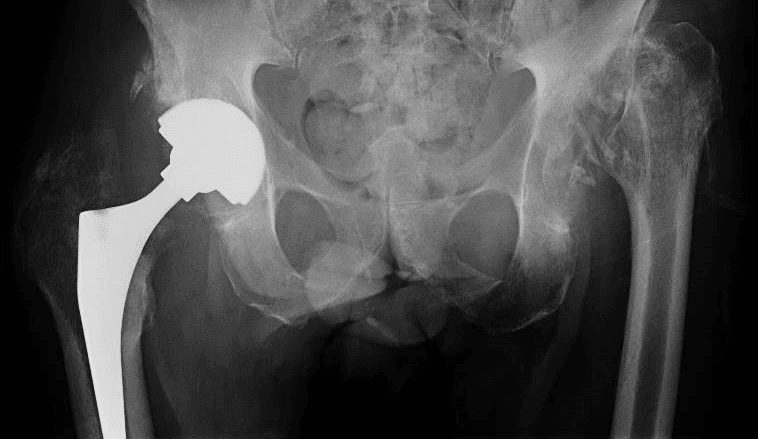

Approccio al trattamento nel nostro centro